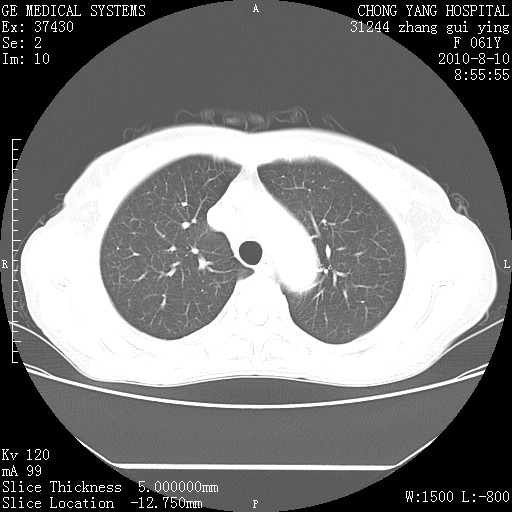

标题: CT28314:F61Y胸部增强,发热咳嗽一周入院,后面的为一周前平 [打印本页]

标题: CT28314:F61Y胸部增强,发热咳嗽一周入院,后面的为一周前平

右肺下叶中心性肺癌可能性大

1、支持考虑右侧中央型肺癌伴右肺中叶节段性不张及下叶支气管黏液痰栓    2、左肺上叶舌段感染。

支持右下肺中央型肺癌并左上肺感染.

我也觉得右肺中叶支气管受累

支持3楼意见,还要考虑:纵隔及肺门淋巴结转移、右侧少量胸腔积液。

支持考虑右侧中央型肺癌

确切的说:1:右肺下叶中心型肺癌侵及中叶支气管并中叶不张,纵膈淋巴结转移。2:左肺舌叶炎症。3:右侧胸腔少量积液

块影平扫32hu,动静脉期62-70hu.

1:右肺下叶中心型肺癌侵及中叶支气管并中叶不张,纵膈淋巴结转移。2:左肺舌叶炎症。3:右侧胸腔少量积液。支持!

右肺下叶内基底段近膈不规则肿块,考虑右肺下叶周围型肺癌可能性大。

考虑右下肺肺癌,纵隔淋巴结转移i。

右肺下叶中心型肺癌侵及中叶支气管并中叶不张,纵膈淋巴结转移。2:左肺舌叶炎症。3:右侧胸腔少量积液